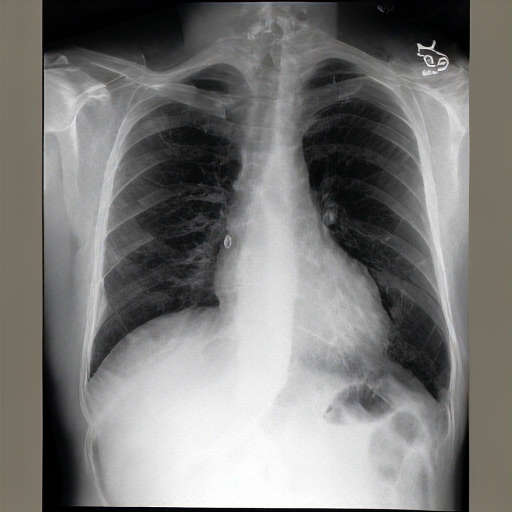

The lungs are well expanded and appear clear. Cardiomediastinal silhouette and hilar contours are otherwise unremarkable. No pleural effusion, or pneumonia pneumothorax. IMPRESSION: No acute cardiopulmonary process or evidence of traumatic injury or acute aortic abnormality are. Consider CT to be in etiology and sensitivity for fractures.

Right central venous catheter terminates in the right atrium. No pneumothorax. Overall low lung volumes are stable. Diffuse right paratracheal and pulmonary mass is better assessed on recent prior chest imaging. No underlying consolidation is identified. Retrocardiac opacity represents atelectasis and may also be secondary to patient rotation and low lung volumes. No pleural effusion or pneumothorax. Left-sided lateral airspace opacities persist which may relate to the known effusions. Mediastinal contours are unremarkable.